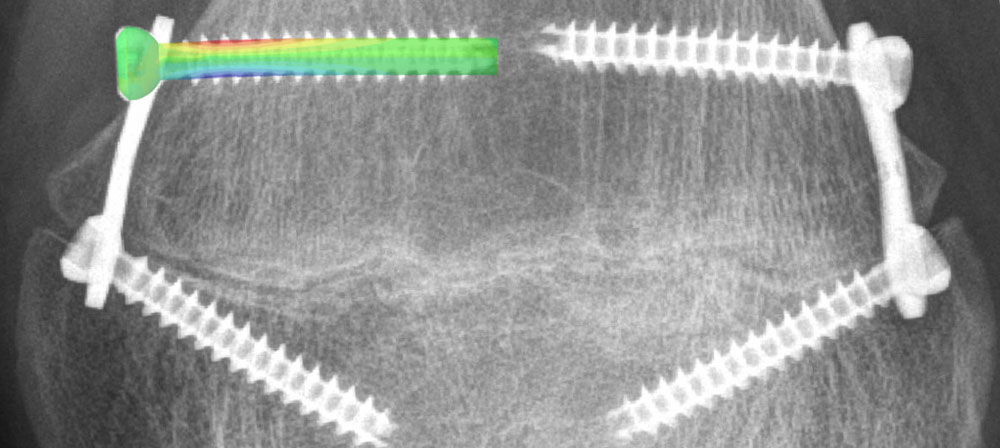

A variety of clinical problems are addressed by the development of new concepts, approaches, tools, and novel implant systems for surgical applications and research in traumatology and orthopedics. The process of finding optimal solutions to clinical questions is enhanced by capabilities ranging from in silico methods to state-of-the-art anatomical labs for quick and effective hands-on work when an anatomical environment is required. Specifically, tailored test procedures involving the implementation of supplemental X-rays, video, and motion tracking systems are applied in diverse experiments on fracture fixation and joint reconstruction. State-of-the-art technologies, powerful numerical methods, and comprehensive tools for virtual simulations are integrated in order to answer various questions with special reference to biomechanical behavior of bone-implant constructs.

Modalities for medical imaging, processing, and analysis, including CT scanners with a wide range of resolutions and scanned volumes, are interlinked to account for increasingly sophisticated demands for morphological investigations, extract statistical and individual information from medical image data and extend the knowledge on variations of biomechanical bone characteristics and their role in persisting clinical problems.